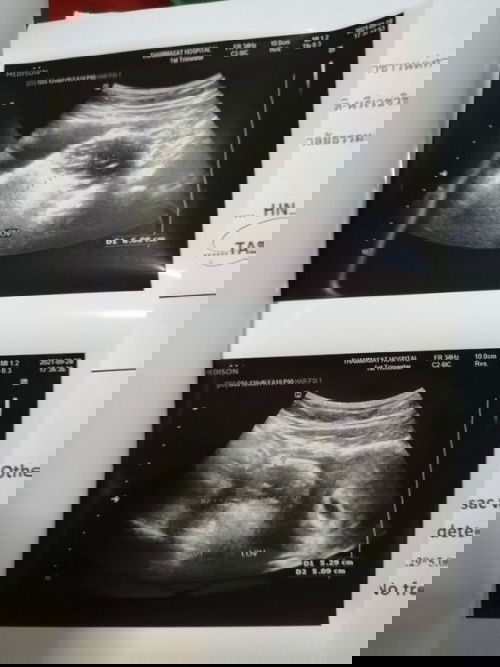

ตอนนี้อายุครรภ์ 12+5W ค่ะ ตั้งแต่ตอนซาวด์ดูน้องครั้งแรก หมอตรวจพบถุงน้ำในรังไข่ฝั่งซ้าย วันที่ 26 ที่ผ่านมาหมอยืนยันผลการตรวจแล้วว่าถุงน้ำเป็นเดอมอยค่ะ (ภายในถุงน้ำจะมีผม กระดูก ฟัน ไขมันอยู่ภายในถุงค่ะ) คุณหมอถามว่าเราจะผ่าตัดหรือเก็บไว้ดี แม่ๆ คิดว่าเราควรทำยังไงดีคะ ถ้าเก็บไว้เสี่ยงบิดขั้ว หรือแตกระหว่างตั้งครรภ์ มดลูกที่โตขึ้นอาจจะไปเบียดถุงน้ำจนแตกได้ ถ้าแตกเราต้องผ่าตัดฉุกเฉิน การผ่าตัดในขณะที่ท้องโตแล้วทำให้ยากในการผ่าตัดค่ะ หรืออีกกรณีถุงน้ำอาจจะเบียดมดลูก ทำให้คลอดก่อนกำหนดได้ ถ้าดีที่สุดคือ ระหว่างตั้งครรภ์ไม่มีปัญหาอะไรเลย รอผ่าตัดออกพร้อมกันตอนผ่าคลอดน้อง แต่ถ้าผ่าตัดก็ต้องผ่าตอนอายุครรภ์ 14-16W ความเสี่ยงคือ เสี่ยงแท้งค่ะ หมอต้องรีบทำการผ่าตัดโดยการตัดรังไข่ฝั่งซ้ายไปเลยค่ะ #ขอคำแนะนำหน่อยค่ะ #ท้องแรกคะ #ขอบคุณล่วงหน้านะคะ #ใครมีประสบการณ์